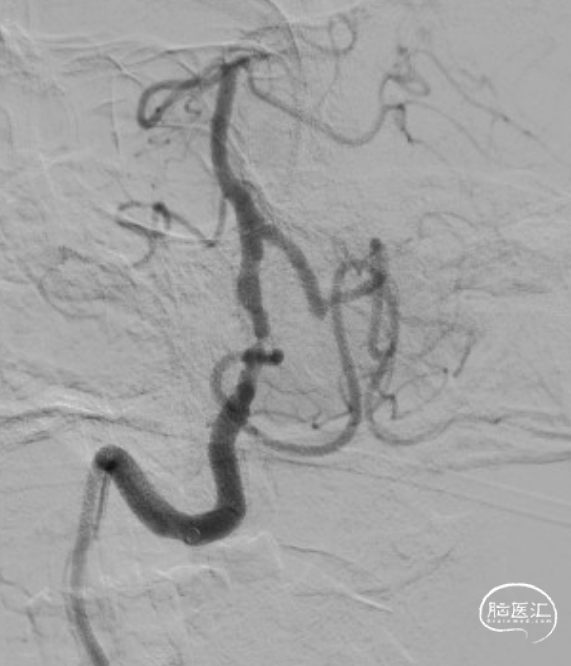

赛诺Neuro LPS®颅内球囊扩张导管 2.75*15mm输送至病变位置。

缓慢扩张至命名压3atm。

球扩后造影观察。